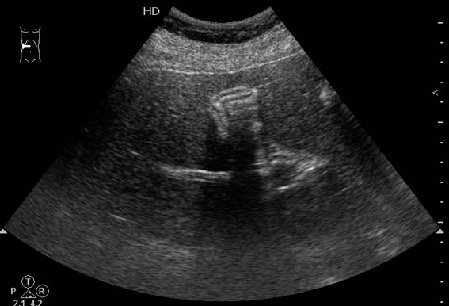

Похожий случай сегодня: